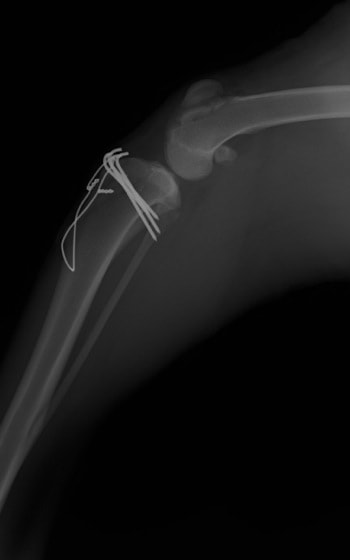

■ 症例22 ポメラニアン 1歳5か月 去勢雄

左後肢の挙上を主訴に来院した。整形学的検査、レントゲン検査より左右の膝蓋骨脱臼(左GradeⅡ〜Ⅲ、右Grade Ⅱ)を認めた。また、脛骨の前方引き出し試験の際に、引き出し兆候は認められないものの、疼痛が認められたため、前十字靭帯の損傷が疑われた。術中における、目視および関節内の操作によって、前十字靭帯の損傷や過伸展といった異常が認められなかったため、膝蓋骨脱臼の整復のみ実施した。手術手技は縫工筋及び内側広筋の解放、脛骨粗面の外側転位、滑車ブロック形造溝術、内外側関節包の縫縮を実施した。本症例は跛行もなく経過良好である。しかし、頸骨高平部の角度(TPA)が 右26.2°、左24.9°であり、解剖学的に前十字靭帯損傷のリスクが高いことから今後の経過に注意が必要である。